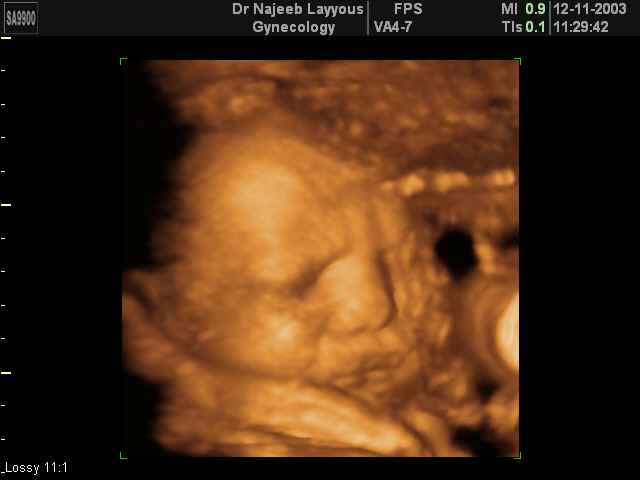

صور لوجه الجنين بجهاز الالتراساوند ثلاثي الأبعاد | الدكتور نجيب ليوس

صور لوجه الجنين بجهاز الموجات فوق صوتية ثلاثي الأبعاد